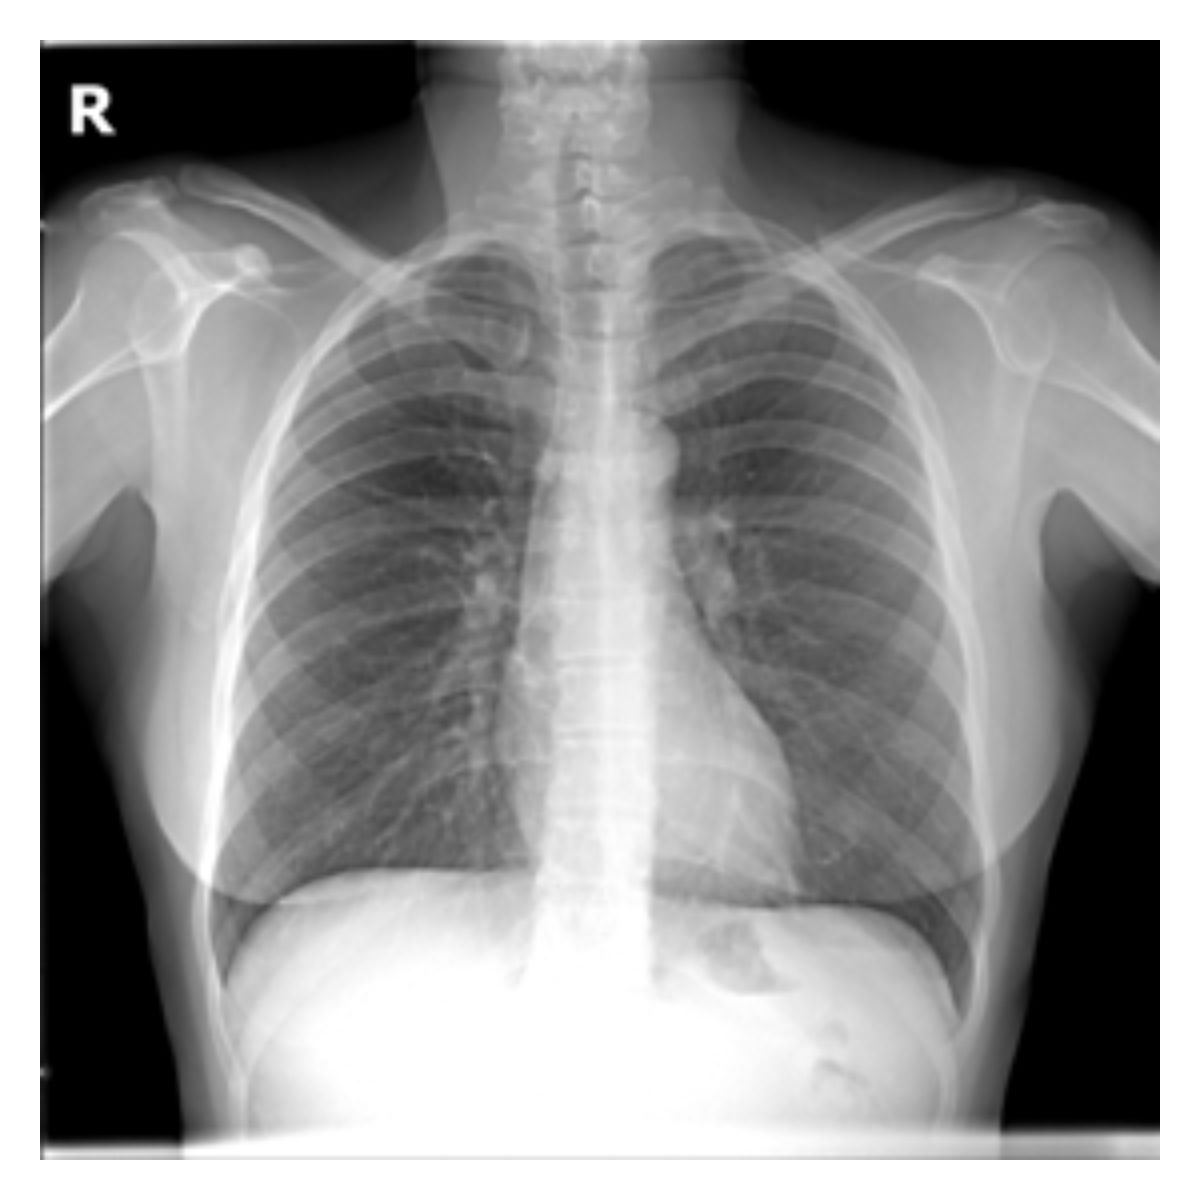

The evaluation of infectious disease processes on radiologic images is an important and challenging task in medical image analysis. Pulmonary infections can often be best imaged and evaluated through computed tomography (CT) scans, which are often not available in low-resource environments and difficult to obtain for critically ill patients. On the other hand, X-ray, a different type of imaging procedure, is inexpensive, often available at the bedside and more widely available, but offers a simpler, two dimensional image. We show that by relying on a model that learns to generate CT images from X-rays synthetically, we can improve the automatic disease classification accuracy and provide clinicians with a different look at the pulmonary disease process. Specifically, we investigate Tuberculosis (TB), a deadly bacterial infectious disease that predominantly affects the lungs, but also other organ systems. We show that relying on synthetically generated CT improves TB identification by 7.50% and distinguishes TB properties up to 12.16% better than the X-ray baseline.